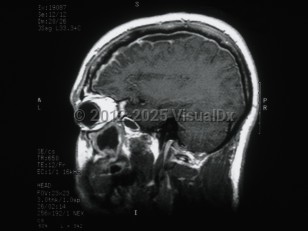

Subdural empyemaSubdural empyema